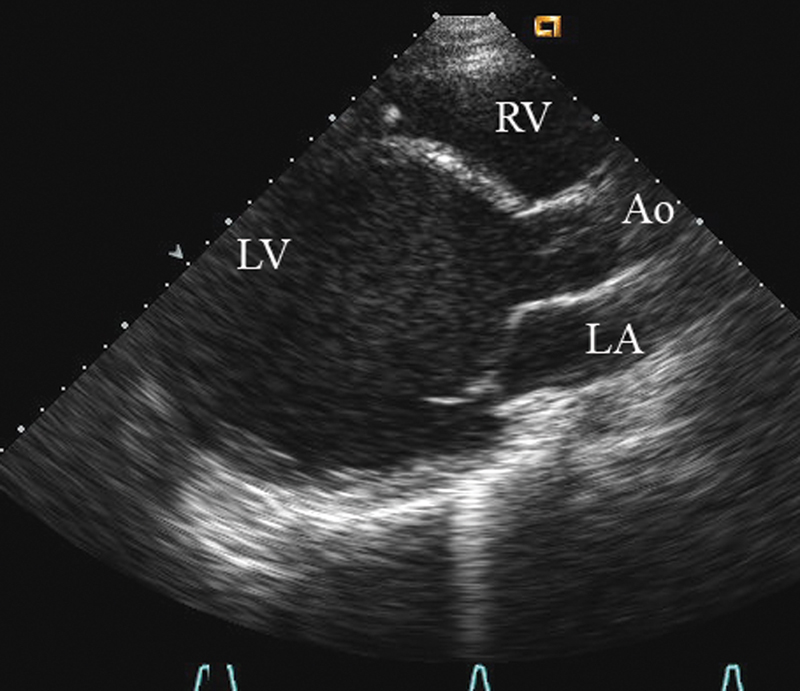

فحوصات تشخيصية لبعض امراض القلب والشرايين التاجية